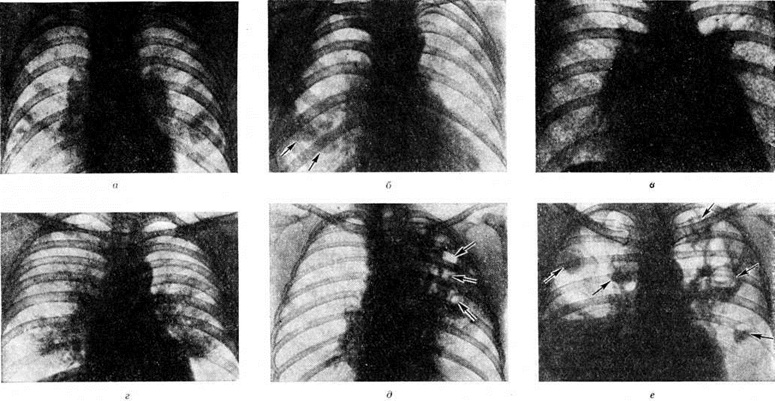

По локализации и объёму поражения лёгких различают следующие формы Пневмония: долевую, или лобарную, Пневмония— при поражении целой доли лёгкого (в этом случае применяют термин «крупозная пневмония»); очаговую Пневмония— при поражении части сегмента, целого сегмента или нескольких сегментов лёгких. В связи с тем, что при очаговой Пневмония обычно поражаются и бронхи, в качестве синонима используется термин «бронхопневмония». Воспалительный процесс при очаговой Пневмония чаще локализуется в нижних долях лёгкого, особенно справа, иногда бывает двусторонним. В случае слияния ряда очагов создаётся впечатление о поражении целой доли (цветной рисунок 1), что обозначается термином псевдолобарная Пневмония (например, при Пневмония, вызванной палочкой Фридлендера). При локализации патологический изменений в строме лёгкого Пневмония называют интерстициальной или межуточной; такие изменения, однако, редко бывают воспалительными в полном смысле слова, как правило, это лимфогистиоцитарно-плазмоцитарные, чаще периваскулярные и перибронхиальные инфильтраты, являющиеся местным проявлением иммунологический реакций. При поражении в основном респираторных отделов лёгких патологоанатомически выделяют альвеолиты — форму Пневмония, характеризующуюся выраженными изменениями альвеолоцитов.

Стафилококковая Пневмония имеет ряд особенностей. На ранних стадиях заболевания вокруг скоплений стафилококков появляется серозный или чаще серозно-геморрагический экссудат с небольшой примесью нейтрофильных лейкоцитов. В дальнейшем очаги воспаления приобретают характерное зональное строение.

В центре их содержится много стафилококков, возникают некротические изменения (рисунок 3, а), вокруг участков некроза накапливаются лейкоциты, которые фагоцитируют стафилококки. В периферических участках пневмонического очага альвеолы содержат фибринозный или серозный экссудат, в котором нет бактерий. При тяжёлом течении болезни (стафилококковой деструкции лёгких) в местах скоплений стафилококков на значительном протяжении происходит разрушение лёгочной ткани. Макроскопически в лёгких выявляются множественные мелкие, нередко сливающиеся очаги абсцедирующей Пневмония Они красного или темно-красного 4 цвета с желтовато-серыми участками расплавления в центральной части. Позднее здесь формируются абсцессы,. принимающие иногда хронический течение. При распространении инфекционные процесса на плевру и её деструкции возникает сообщение между полостью абсцесса, бронхами и плевральной полостью, развивается пиопневмоторакс (смотри полный свод знаний). Иногда в результате деструкции стенки бронха и проникновения воздуха в интерстиций возникает интерстициальная эмфизема.

Стрептококковая Пневмония имеет много общих черт со стафилококковой. Однако в тяжёлых случаях она характеризуется большей степенью некроза клеток экссудата и лёгочной ткани, а также более выраженной лимфогенной генерализацией процесса.

Для Пневмония при острых вирусных респираторных инфекциях (гриппе, парагриппе, респираторно-синцитиальной и аденовирусной) наиболее характерно поражение эпителия слизистой оболочки дыхательных путей и альвеолоцитов. В результате внутриклеточного размножения вирусов происходит повреждение этих клеток с развитием дистрофических и некротических изменений. При благоприятном течении заболевания через несколько дней в них возникают реактивные изменения в виде уплотнения цитоплазмы вокруг участка повреждения — фуксинофильные включения) (рисунок 3, б). Наряду с этим наблюдаются умеренно выраженные воспалительные изменения слизистой оболочки дыхательных путей с преобладанием нарушений кровообращения в виде полнокровия сосудов, выпотевания серозной жидкости в просвет альвеол и небольших кровоизлияний. Отмечаются также небольшие скопления нейтрофильных лейкоцитов и альвеолярных макрофагов. В результате нарушения образования сурфактанта (смотри полный свод знаний) возникают небольшие ателектазы (смотри полный свод знаний), большей частью неполные,— дистелектазы (рисунок 3, в), что особенно выражено у детей раннего возраста, а также компенсаторное очаговое расширение альвеол в других участках лёгких. Макроскопические изменения при этом незначительны и заключаются в основном в катаральном воспалении дыхательных путей и образовании в лёгких небольших участков уплотнения темно-красного или синюшного цвета. Наиболее характерной чертой вирусной Пневмония является гигантоклеточное превращение поражённых эпителиоцитов.

При гриппе поражённые клетки несколько увеличиваются в объёме, в случае же отторжения превращаются в крупные одноядерные клетки, значительно превышающие по размерам обычные альвеолярные макрофаги (рисунок 3, г). Для парагриппа типичны подушкообразные разрастания, сосочковидные выросты слизистой оболочки. При респираторно-синцитиальной инфекции они ещё более выражены. При аденовирусной Пневмония происходит образование крупных одноядерных клеток (гигантоклеточный метаморфоз альвеолоцитов), а также выраженное накопление экссудата (рисунок 3, д). При выздоровлении происходит регенерация эпителия дыхательных путей. Вначале выявляются недифференцированные уплощённые эпителиальные клетки, располагающиеся обычно в несколько рядов (рисунок 3, е), которые в дальнейшем дифференцируются .

Изменения, сходные с морфологический изменениями при вирусной Пневмония, наблюдаются при микоплазменной Пневмония — респираторном микоплазмозе (смотри полный свод знаний Микоплазменные инфекции). Для неё также типично внутриклеточное размножение возбудителя (рисунок 4), хотя возможно и внеклеточное. Поражения носят характер десквамативной Пневмония при весьма умеренных макроскопических изменениях (цветной рисунок 3—5; 6—10).

Стрептококковая Пневмония встречается редко и в большинстве случаев является осложнением кори, коклюша, гриппа, а также различных острых респираторных или хронический болезней. Бронхогенное распространение инфекции приводит к появлению мелких пневмонических очагов в пределах одного сегмента и быстрому распространению инфекции по всему лёгкому с образованием сливных очагов (цветной рисунок 2). Поражаются главным образом нижние доли лёгких. Стрептококковая Пневмония начинается остро с лихорадки, повторных ознобов, выраженной интоксикации, болей в боку и кашля с отделением жидкой, с прожилками крови мокроты, содержащей большое количество стрептококков. Заболевание в 50— 70% случаев осложняется выпотным плевритом. Признаки плеврита появляются на 2—3-и сутки болезни. В жидком серозном или серозно-геморрагическом выпоте содержится большое количество микроорганизмов. Аускультативная симптоматика скудная. Притупление перкуторного звука нередко обусловлено выпотным плевритом. Характерен высокий лейкоцитоз с выраженным сдвигом лейкоцитарной формулы влево. В 10—15% случаев обнаруживается бактериемия.